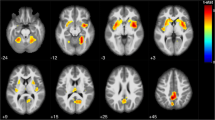

In the MS group, the correlation analysis showed a positive association between SDMT score and regional GM volume in the following brain regions (Fig. 1, Table 2): the posterior lobe of the cerebellum, bilaterally; the thalamus, bilaterally; the left lateral occipital cortex, the occipital pole, bilaterally; the right occipital fusiform gyrus and the left putamen. On the contrary, no correlations were found between SDMT and regional GM volume in the HC group.

Regional pattern of gray matter (GM) volumes positively associated with Symbol Digit Modalities Test (SDMT) Z-scores in multiple sclerosis (MS) patients, superimposed on the customized GM template. Legend: The regions showing significant correlations (p < 0.05) are shown in red–yellow (t-value 0–6). Abbreviations: A = anterior, P = posterior, L = left, R = right, S = superior, I = inferior

Our results showed that lower performance in SDMT was associated with a reduction of GM volumes in the cerebellum, bilaterally (posterior lobe), the thalamus, bilaterally, the left putamen and the occipital cortex.